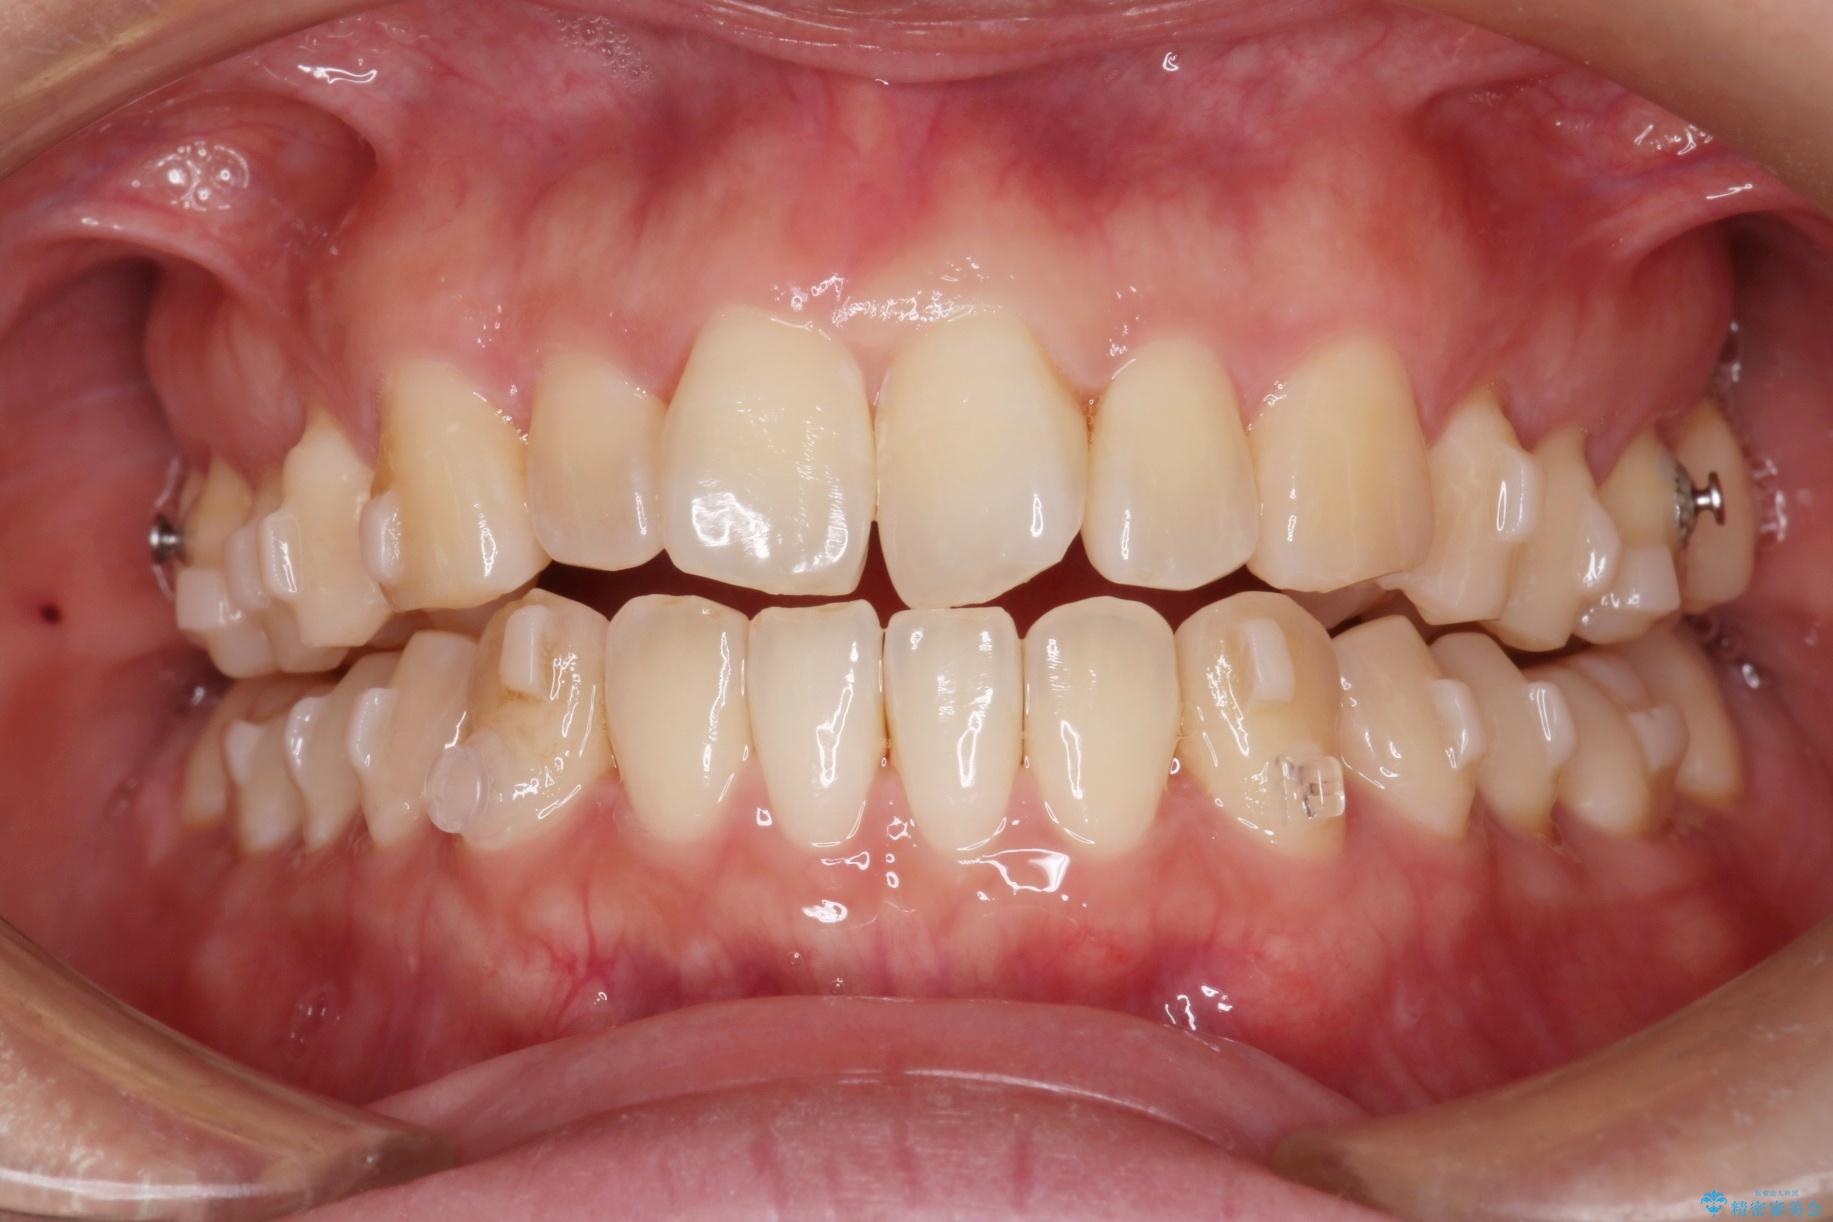

上の前歯のねじれが気になるとご来院された患者様です。

治療計画

前歯の捻れとがたつきを改善するために、IPR(歯と歯の間を削る処置)と歯列拡大をすることで歯並びを整えていく治療計画を立てました。